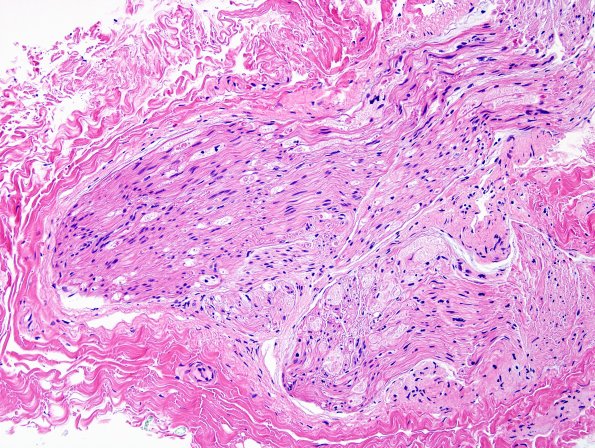

Case 6 History ---- The patient is a 40-year-old female who had a progressive course starting one year previously consisting of numbness and paresthesias in bilateral feet > hands, initially involving the right hand and left foot only, but over the next 1-2 weeks, progressed to involve both hands and feet symmetrically. She has shooting and stabbing pain but no associated weakness except for difficulty with fine motor tasks due to numbness in her hands and keeping her balance due to numbness in her feet. EMG in 11/2010 showed progressive severe sensory neuropathy/ganglionopathy. There was a clinical concern for CIDP. Operative procedure: Left sural nerve and left gastrocnemius muscle biopsy. ---- 6A1,2 The sural nerve specimen showed numerous degenerating axons. (H&E)